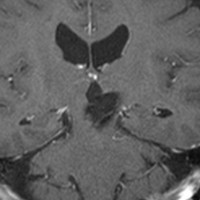

脳幹部の海綿状血管腫を手術するとき

左上のT2*でみられるように多発性海綿状血管腫の成人男性に発生した中脳海綿状血管腫です。複視と歩行失調で発症して,数回の脳幹部出血を繰り返し,水頭症になったために第3脳室開窓術がなされました。それでも出血は止まらず、両側の動眼神経麻痺による両側眼瞼下垂,歩行失調,嚥下障害などさまざまな中脳症状が進行しました。

しかたがないので手術で摘出しました。なんとか眼瞼が持ち上がるようになり歩行も可能で嚥下もできます。幸いだったのは感覚路(脊髄視床路)の障害による体性疼痛が生じなかったことです。

手術は経テント法 OTA という手法でした(クリックと手技が書いてあります)

片方の下丘の損傷だけでは神経脱落症状が出ないので,中脳内部の腫瘍を摘出するには下丘という狭い場所を切開して入りますが,この患者さんは左上丘も出血のために破壊されていて,間口が広かったといえます。でもこの手術は難しすぎるので決して積極的にはしません。